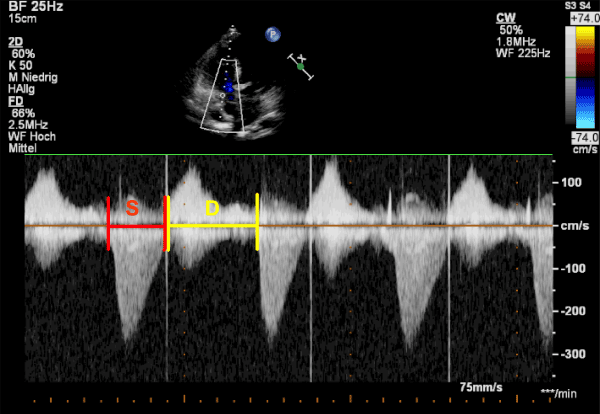

| Figure 5: Apical 4-chamber view. Doppler-derived tricuspidal regurgitation time (TR) interval ratio of systolic (S) duration to diastolic (D) duration (S/D) The ratio of S/D duration was calculated by dividing the duration of the TR spectral Doppler flow pattern by the time interval of the cardiac cycle that did not include TR. Systolic and diastolic duration using TR duration was measured by CW-Doppler from the apical 4-chamber view to calculate the S/D ratio. The red lines show the systolic duration, the yellow lines show the diastolic duration. |